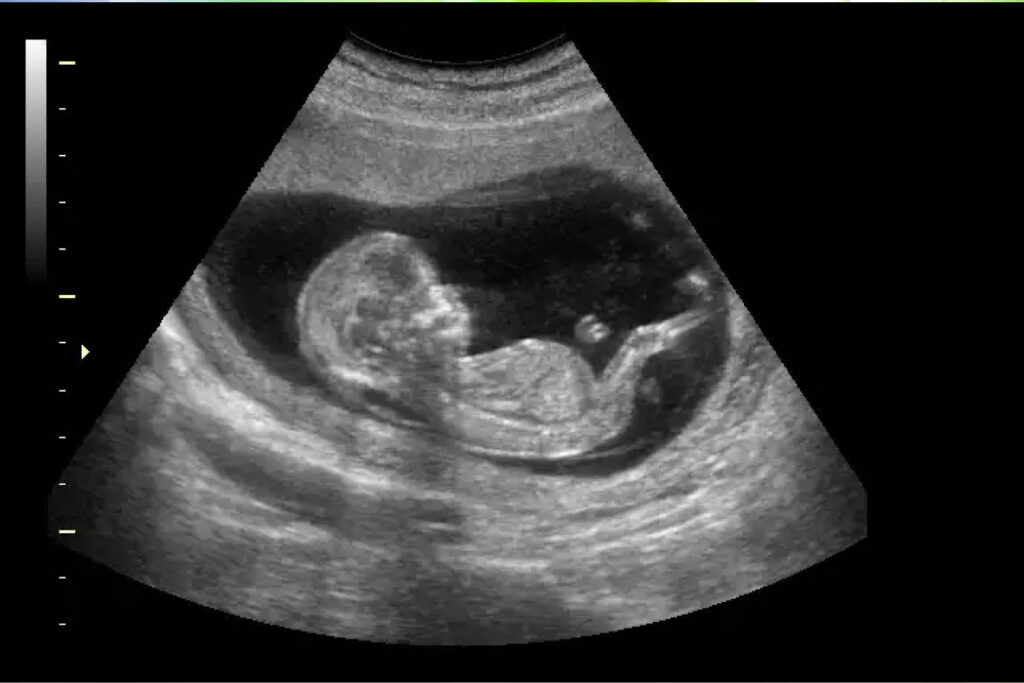

En su intervención de medio día, la vicepresidente de Nicaragua, Rosario Murillo, destacó que se estarán entregando 200 válvulas para corregir defectos de los bebes para que nazcan sanos.

“También como parte del Programa Nacional de Cirugías en el Vientre Materno se entregarán 200 válvulas altamente especializadas”, resaltó la vicemandataria.

Destacó que estas válvulas son para corregir defectos como hernias y alteraciones en el corazón, en los bebes. Este proceso se realiza cuando están aún en el vientre de las madres para que nazcan sanos y fuertes.